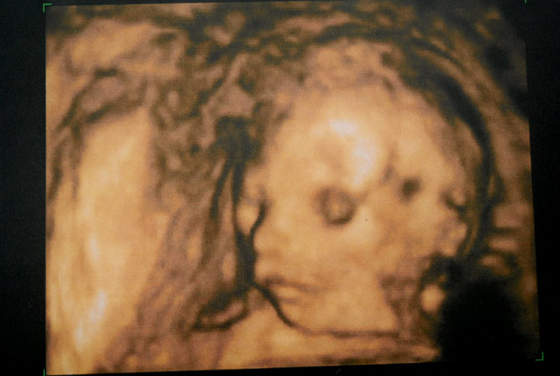

Oto mój Skarbuś na badaniu USG 3D - zdjęcie troszkę niewyraźnie, ale to dlatego, że się ruszał :-) Takie "żywe sreberko" nam rośnie ;-)